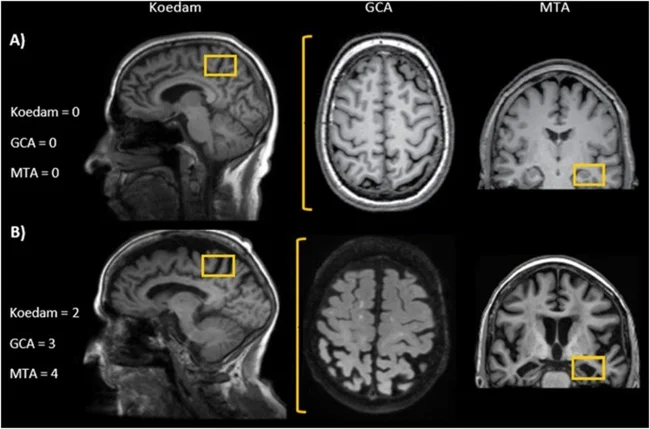

An analysis of over 12,000 MRI scans from nearly 5,000 healthy people aged 17 to 95 showed that brain volume declines faster in men than in women. Specifically, men exhibit greater loss of gray and white matter in more regions, including the cerebral cortex and subcortical structures.